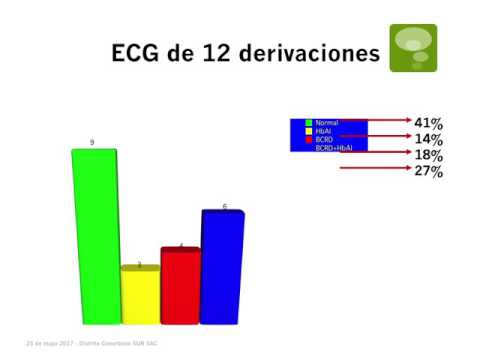

Paciente de 68 años con miocardiopatía dilatada chagásica, FA y TVNS. Dr. Remberto Torres Molina. Santa Cruz de la Sierra. Bolivia